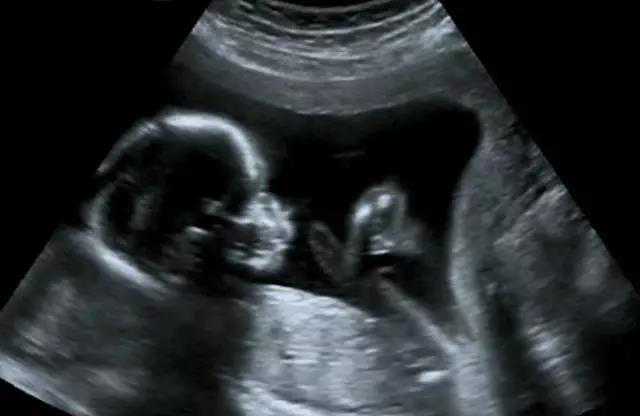

B超像挑西瓜前敲一敲

B超检查是利用超声波产生回声的原理来检查的。超声能向一定方向上传播,而且可以穿透物体,如果碰到障碍,就会产生回声,人们通过仪器将这种回声收集并显示在屏幕上,可以用来了解物体的内部结构,辅助诊断。就像挑西瓜一样,边敲边看显示病灶情况。B超是两个维度的超声信息,构成平面图形,反映人体结构。

随着彩色-多普勒超声技术的产生,出现了彩超(彩色B超),即在黑白B超的基础上加上彩色多普勒,彩超同时又提供了血流动力学的丰富信息,实际应用受到了广泛的重视和欢迎,彩超在目前临床上经常被使用。